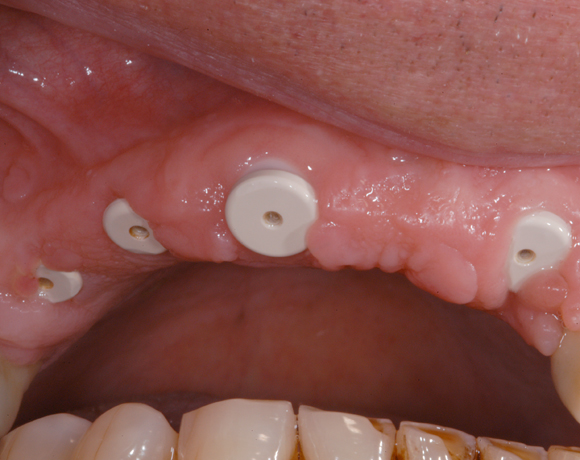

6 Implantate und viele Kronen und Brücken

Mit dem zweiteiligen vollkeramischen Implantat lassen sich auch große Lücken überbrücken.

Im vorliegenden Patientenfall waren die Zähne 11 – 26 mit einer provisorischen Brücke versorgt, der Patient konnte damit aber nicht essen. Auch im Unterkiefer waren die vorhandenen Kronen und Brücken insuffizient. Es wurde eine komplette Neuversorgung für Ober- wie Unterkiefer geplant.